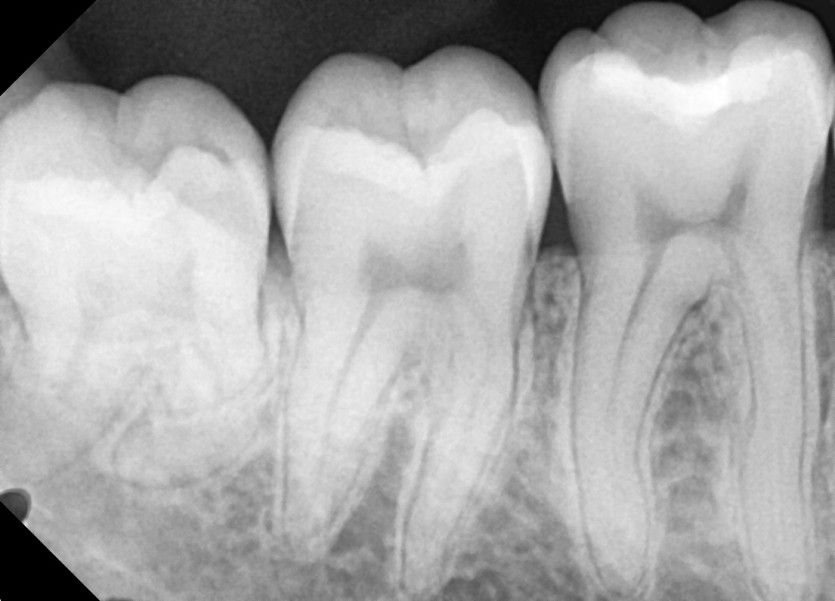

#18,28,48 사랑니 발치

구강 외과 전문의가 당일 발치했습니다.